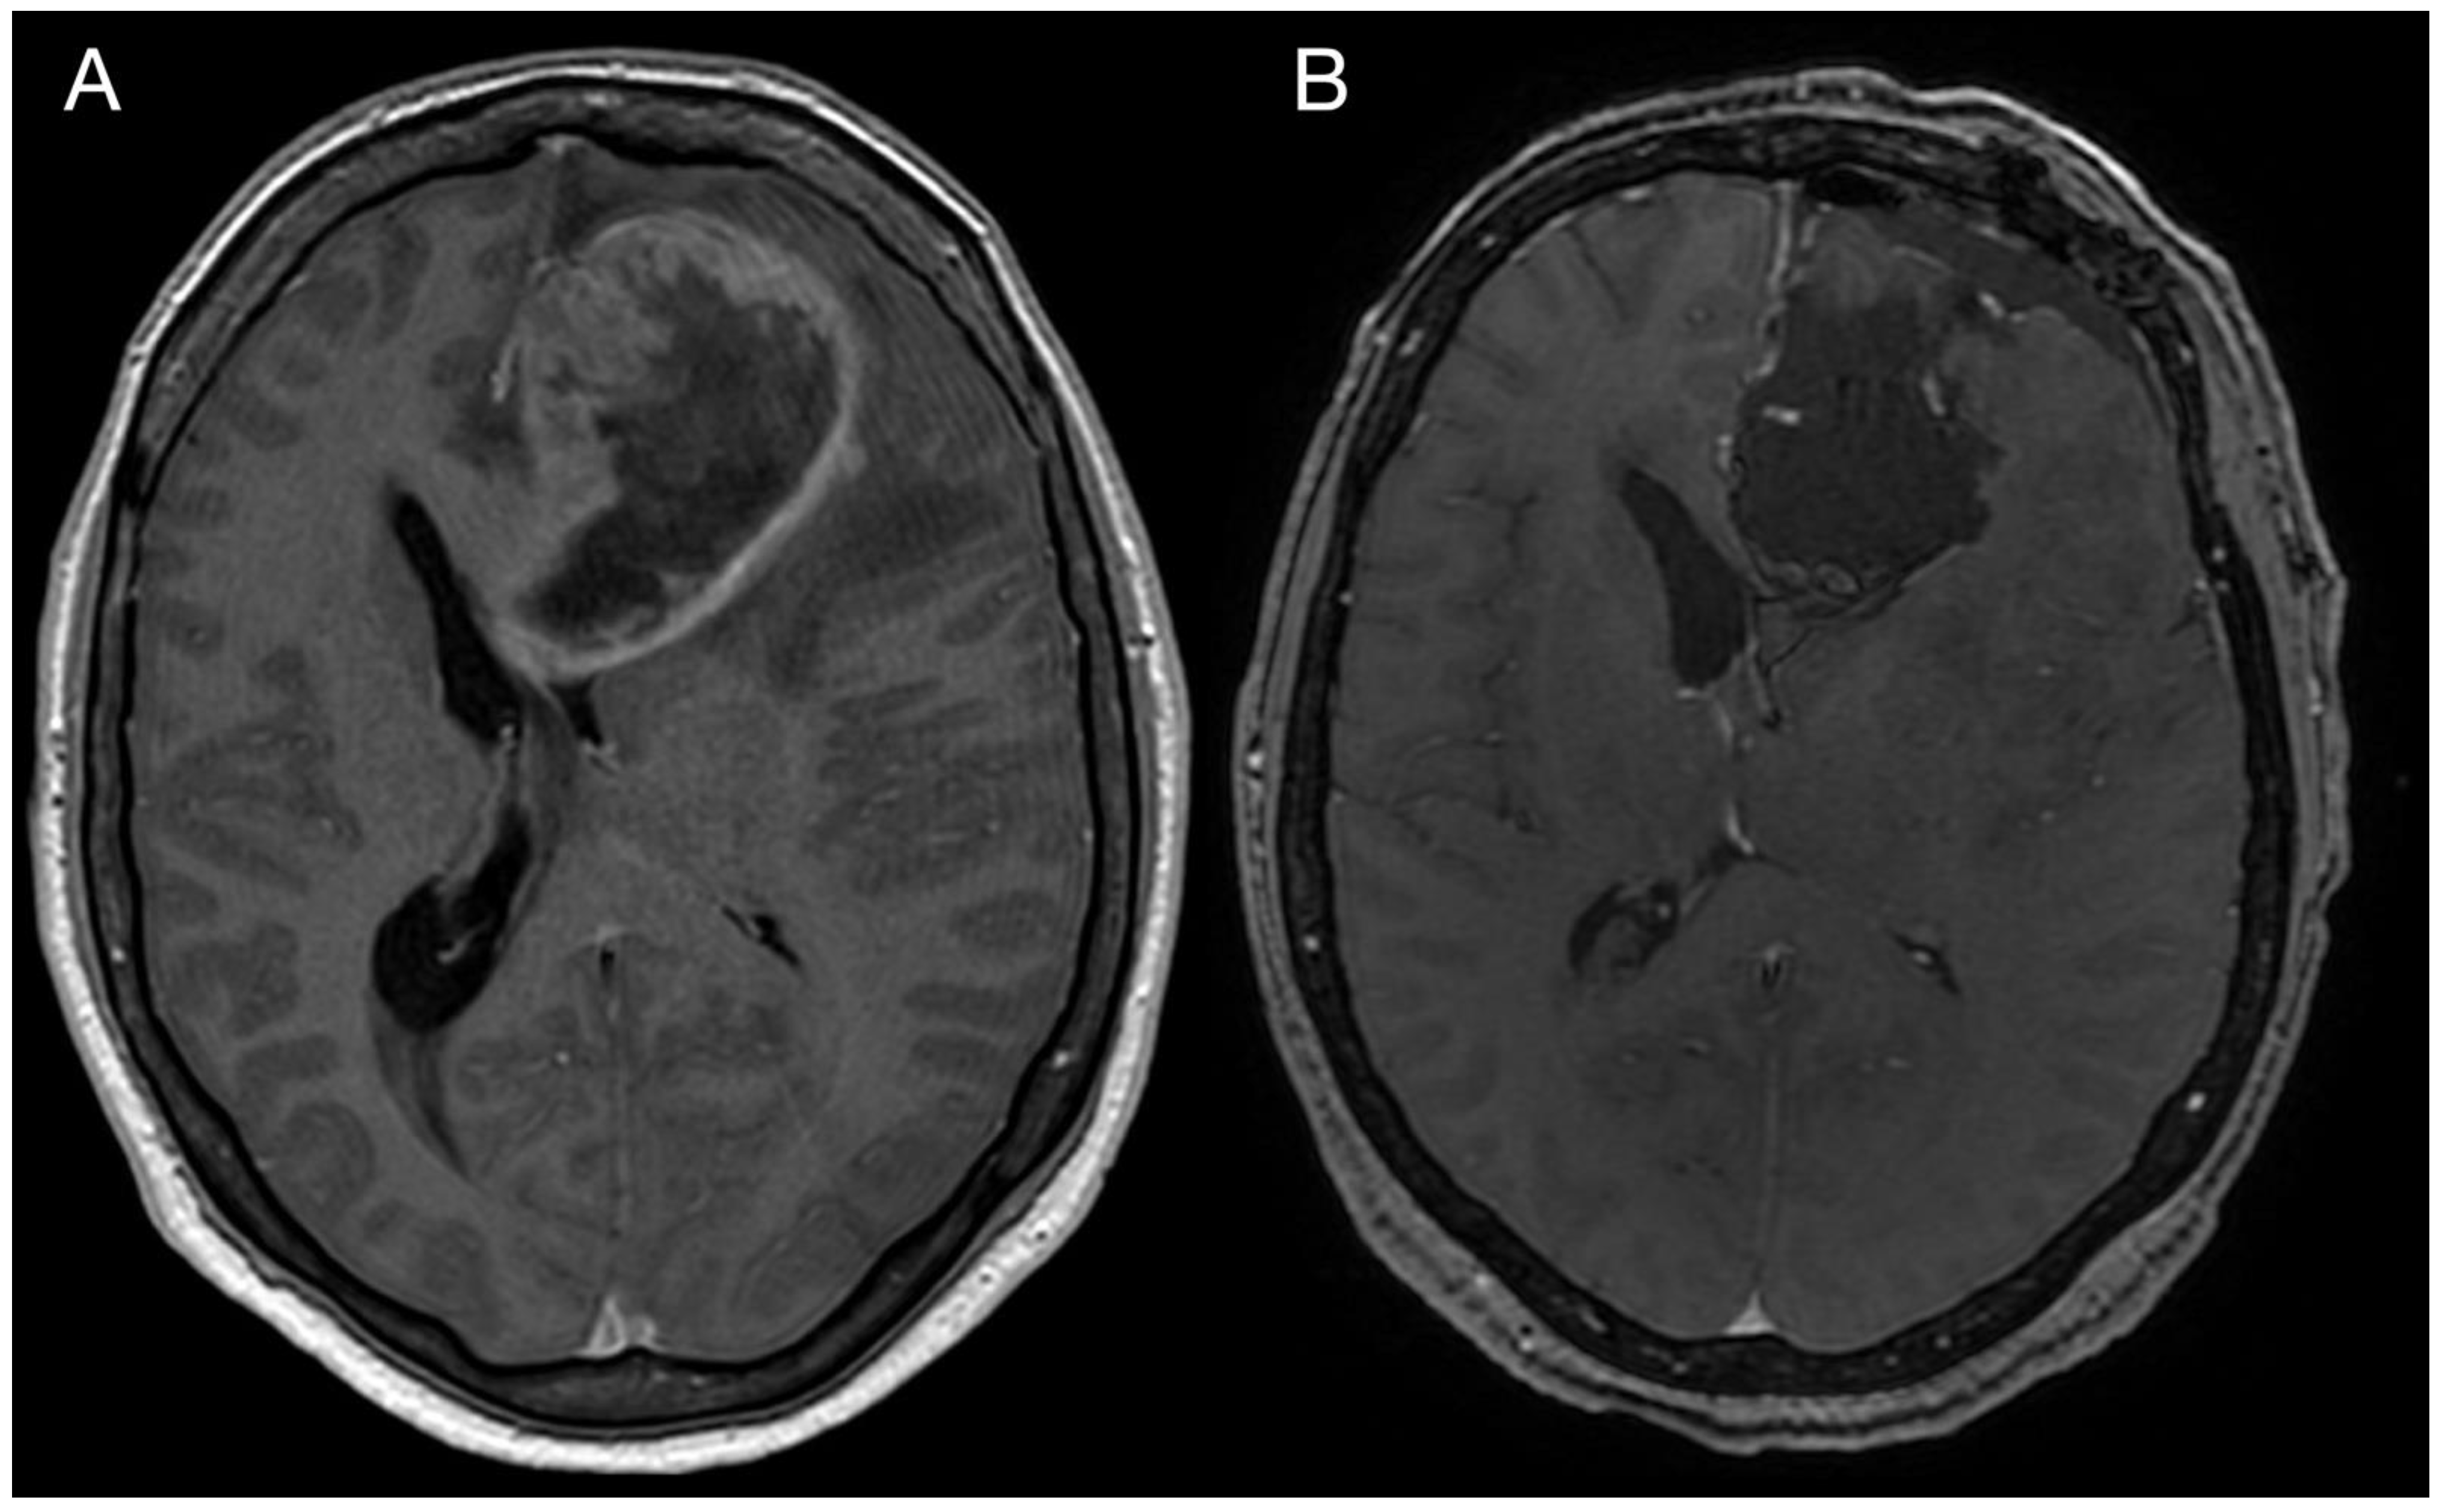

2. Case Report